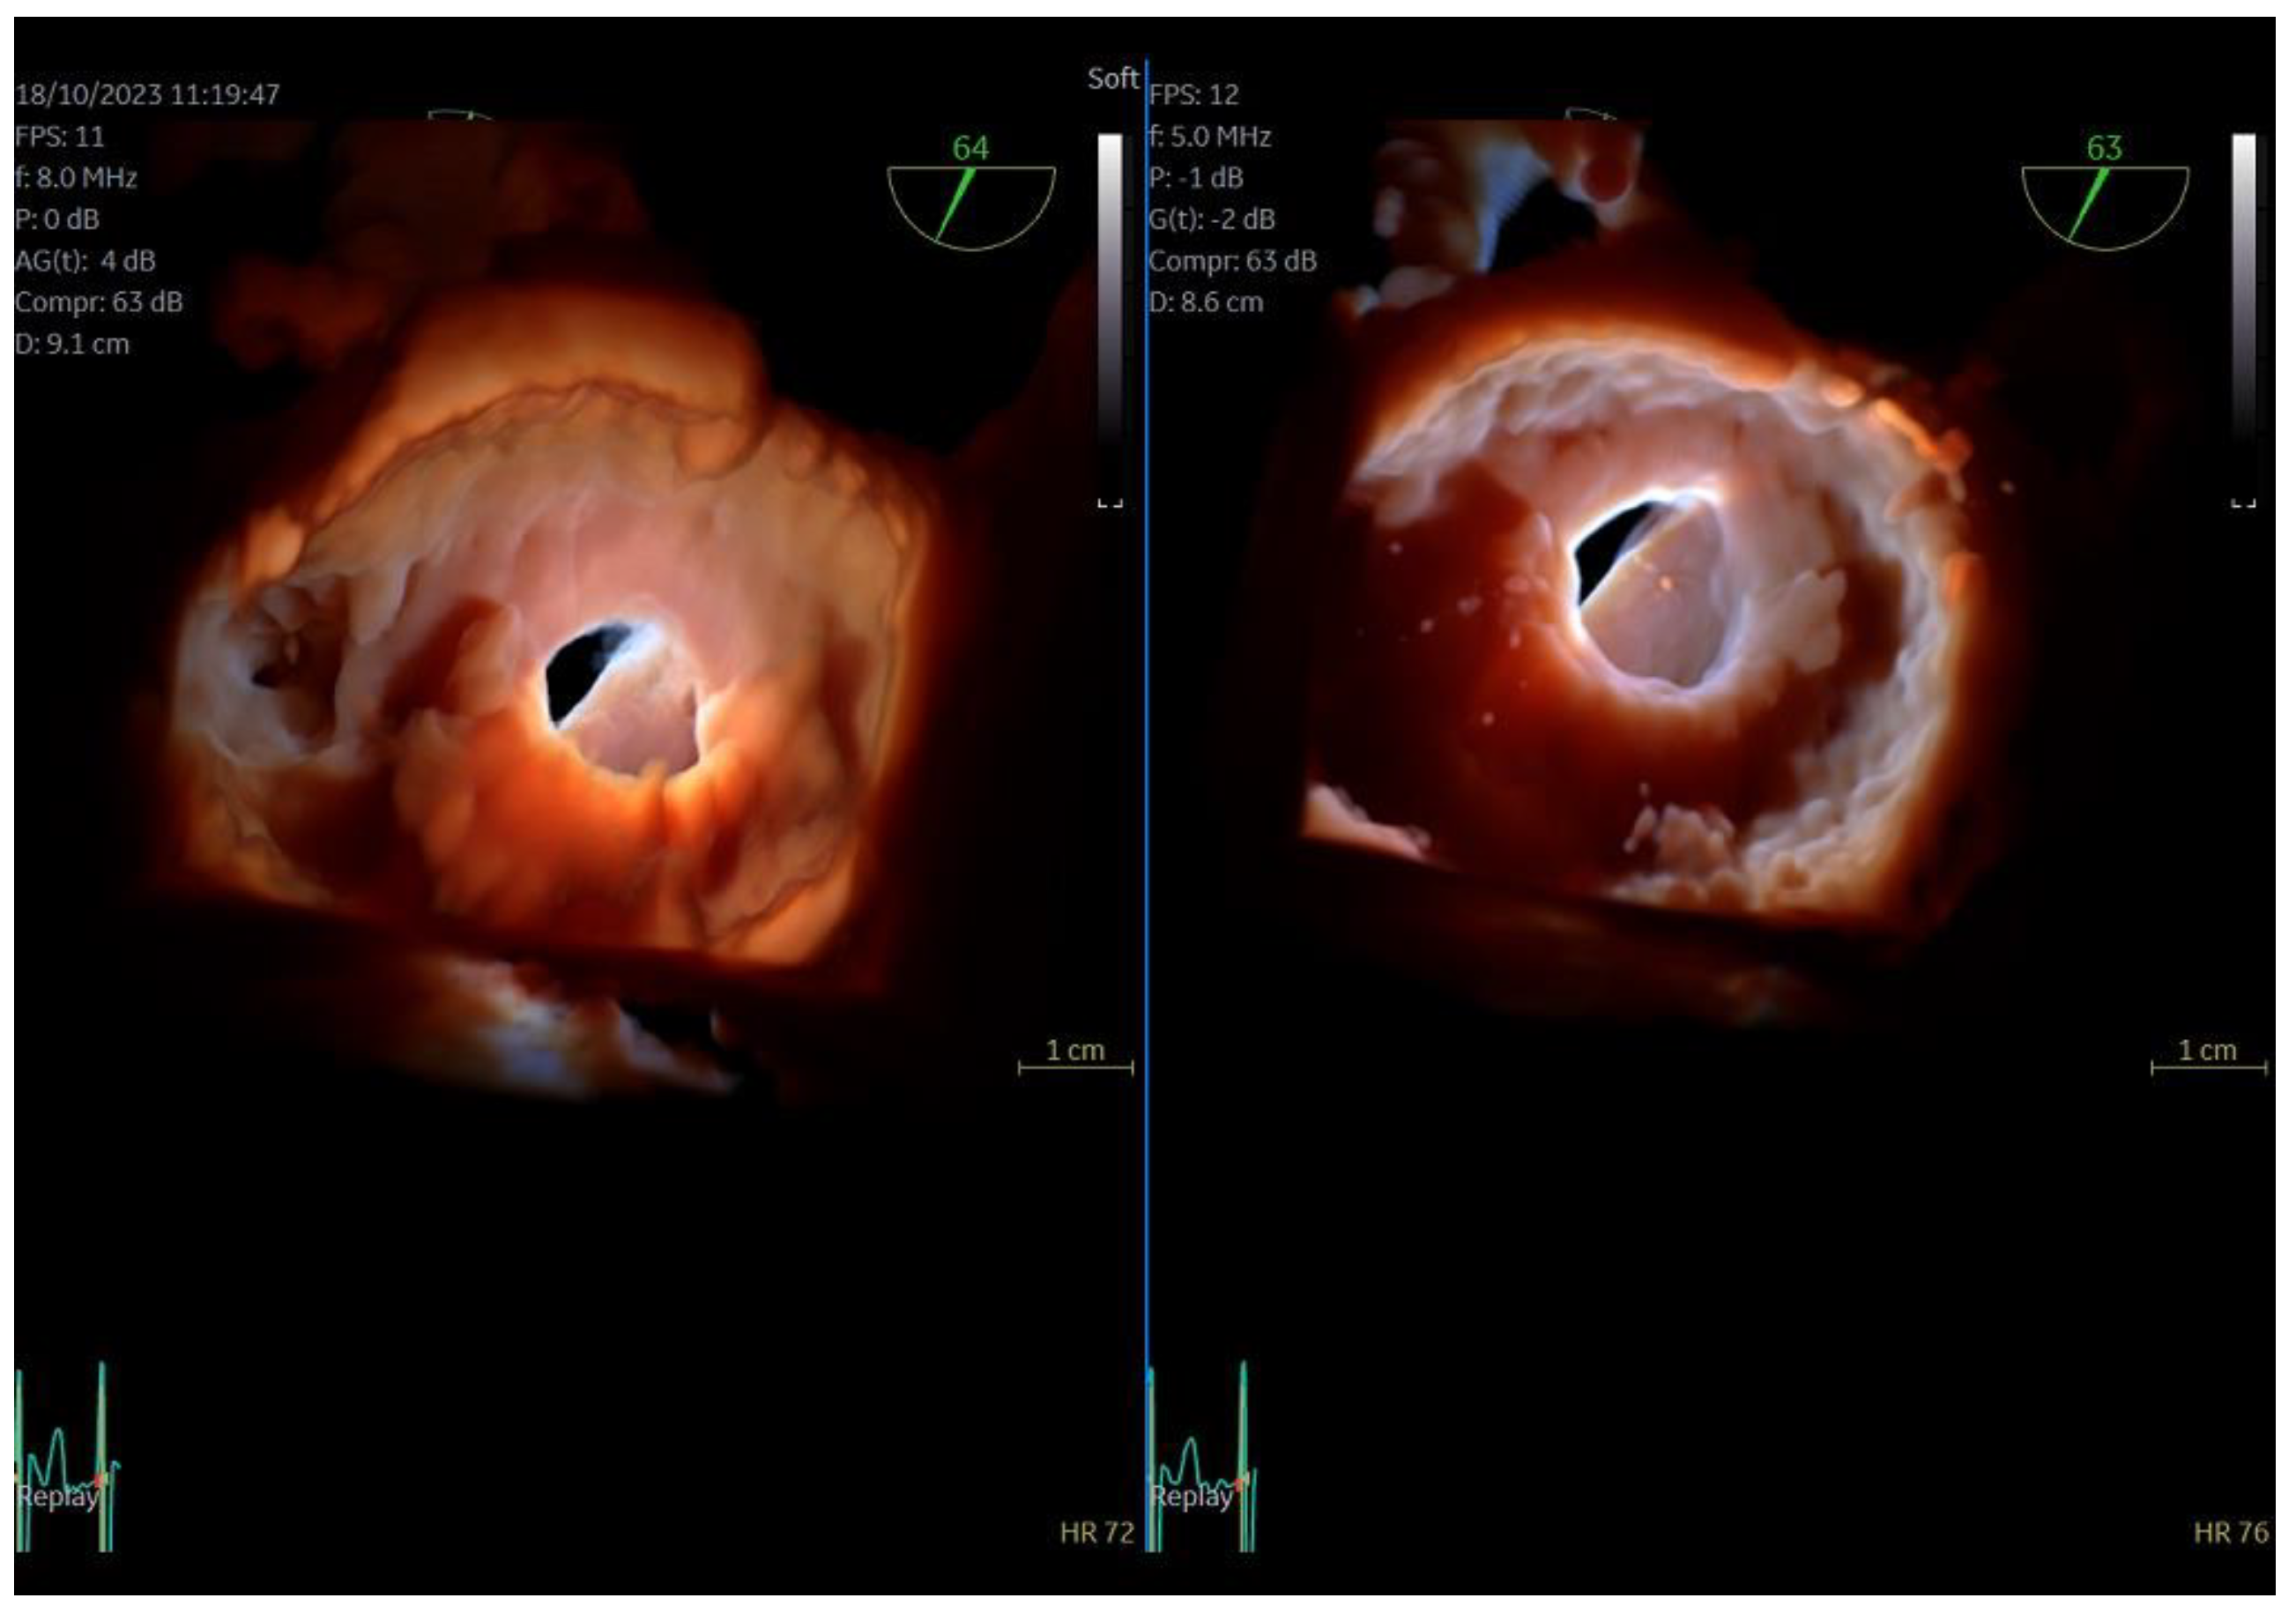

Figure 2.

Direct comparison of 3D volume-rendered “en face” images of a metallic prosthetic mitral valve with occluded disk. Left image corresponds to 6VT−D adult probe and right image corresponds to 9VT−D pediatric probe. Images enhanced with “photorealistic method” with Flexilight application (GE Healthcare).

The quality of images obtained with the 9VT-D pediatric probe and the accuracy of findings were assessed through examination of the first three patients. Each patient underwent a comprehensive TEE protocol using both the pediatric 9VT-D and adult 6VT-D probes, allowing for direct comparison of findings and image quality. Throughout the procedure, patients received local oropharyngeal lidocaine and mild sedation with midazolam to ensure tolerance.

The adult probe was initially inserted for complete 2D/4D image acquisition, followed by the insertion of the pediatric probe while the patient remained under sedation. Remarkably, insertion of the pediatric probe was effortless in all cases, requiring no additional sedation. Despite encountering challenging diagnostic scenarios in all three cases (1st patient: combined severe aortic stenosis and severe mitral regurgitation (MR) due to P1 scallop prolapse, 2nd patient: malfunction of metallic mitral valve prosthesis with an occluded disk, 3rd patient: bioprosthetic aortic valve with paravalvular leak and significant MR in previously MV repair with a complete ring), the pediatric probe consistently provided high-quality images comparable to those obtained with the standard adult probe (Figure 1 and Figure 2, video S4). Notably, there was no compromise in 2D and 4D spatial and temporal resolution, with only minor differences observed compared to the adult 6VT-D probe (Table 1). Evaluation using the 5-point scoring system consistently yielded an average score close to 5 for all three cases, indicating excellent image quality (Table 1).